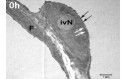

Die chemokininduzierte Einwanderung neutrophiler Granulozyten in die Lunge ist ein zentraler pathophysiologischer Mechanismus im Rahmen des akuten Lungenversagens. Die zentrale Bedeutung von DARC für die Konzentration zirkulierender Chemokine impliziert eine mögliche Rolle bei der Entstehung des akuten Lungenversagens.

Dieses Projekt soll die Bedeutung von DARC im ARDS charakterisieren.